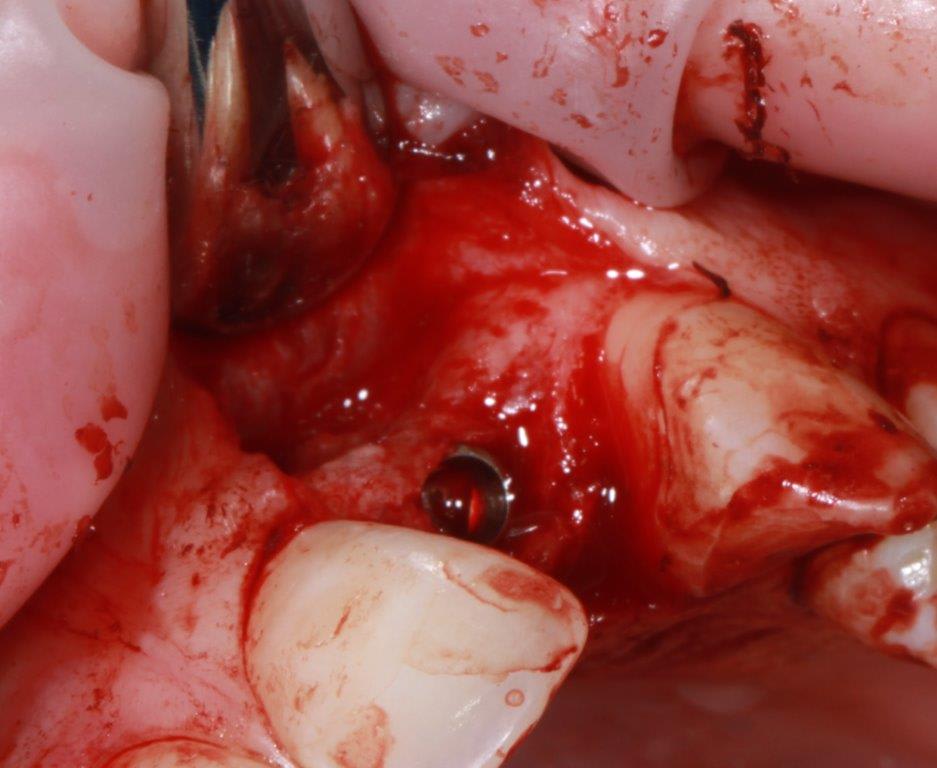

pour ceux que ça intéressent, une petite utilisation d'expansion de la paroi palatine, sur une avulsion d’incisive(racine fendue). toutes mes excuses pour la mauvaise qualité des photos.